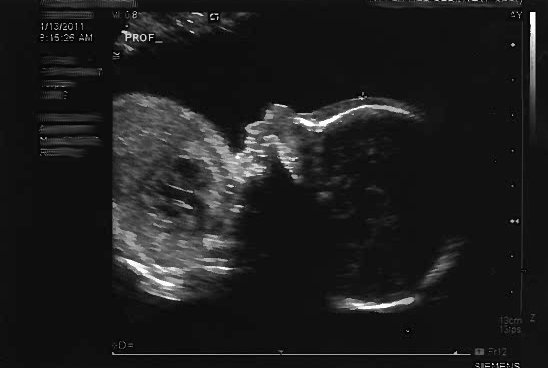

13 January 2011 – Another FANTASTIC day! You had your “big” photo shoot!

Mom & Dad went to this super cutting-edge, hi-tech medical appointment. The person in the medical office used a magic wand on Mom’s belly to create images of you inside.

It was your 20-week “ultrasound” (or “Fetal Survey” as they say in the obstetrical world). Basically they used cyclic sound pressure with a frequency greater than the upper limit of human hearing. Although this limit varies from person to person, it is approximately 20 kilohertz (20,000 hertz), but you know this already, of course.

Mom had SUCH a fun time seeing the detail that goes into the ultrasound and your dad asked so many questions. Being that your mom works closely with the perinatology office that did the ultrasound, your parents felt they got a little VIP treatment during the appointment. One of your mom’s favorite perinatologists, Dr. Harding, read the ultrasound and was happy to tell us you look PERFECT! The ultrasonographer, Allison, said you should be in a textbook, which made your dad VERY proud. Your mom jokingly reminded your dad that being in medical textbooks isn’t always a good thing… but we know you’re happy and healthy in there!

You’re being shy in this picture and have your forearms in front of your face.